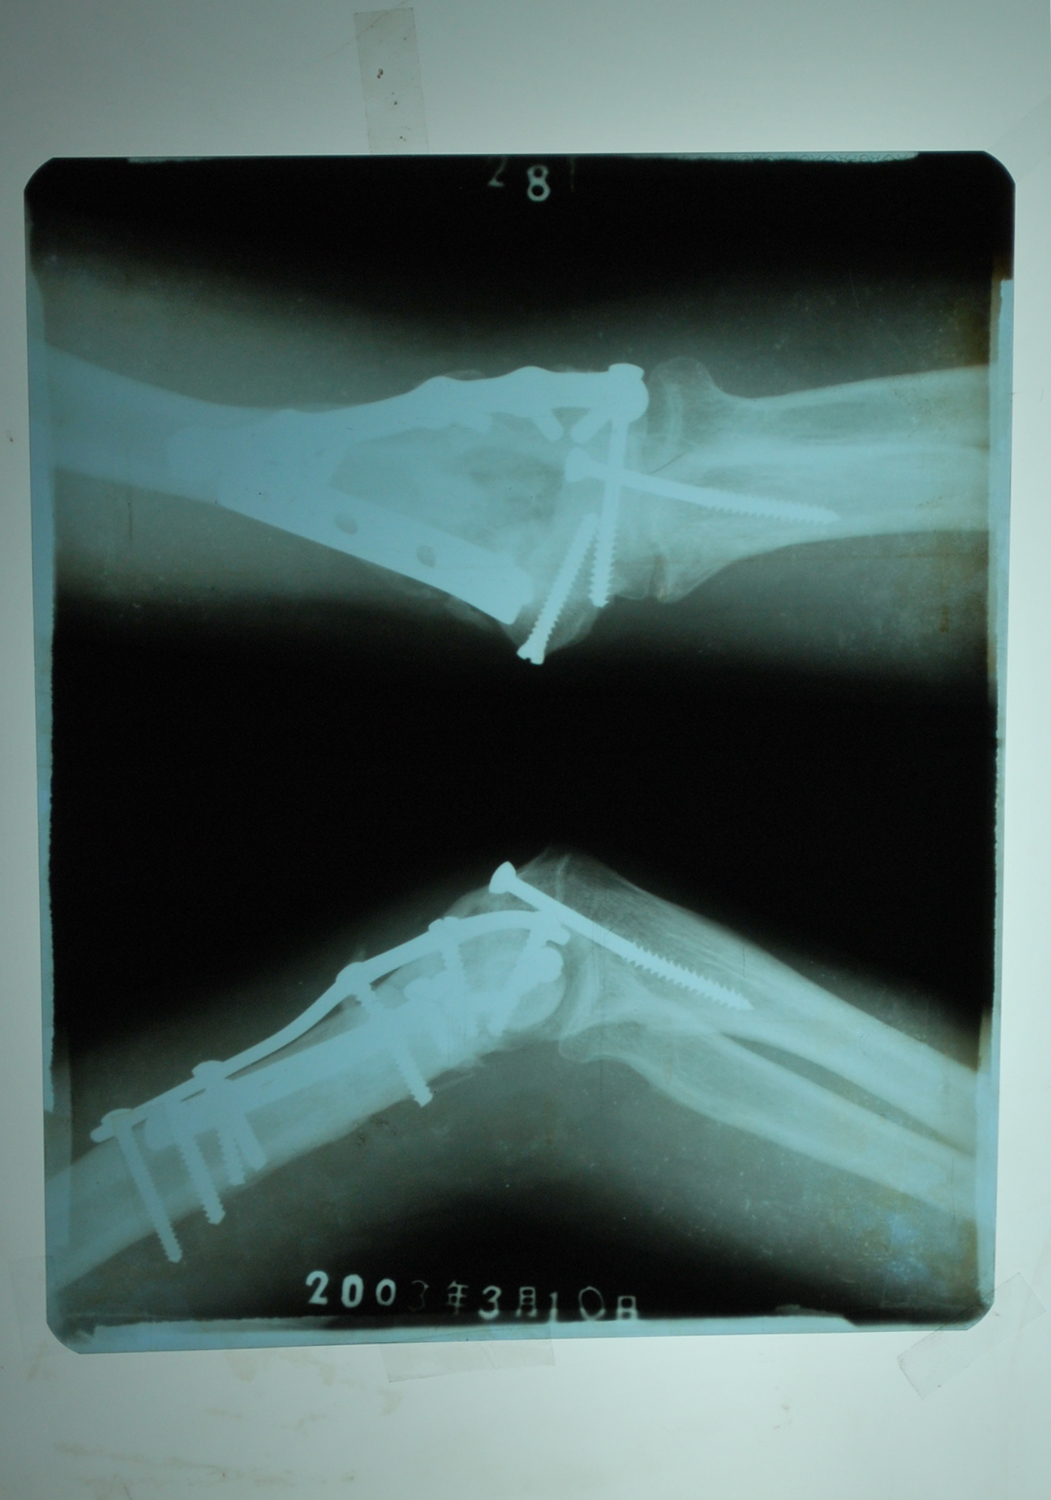

第二天早上,恶警还要给贾志君上绳迫害,贾志君抗议迫害,被迫从公安局三楼跳下。医生诊断右肘骨折,他在伊春医院上两块钢板,十三个钢钉。毫无人性的恶警不顾贾志君死活,上完钢板二天就把他劫持到金山屯区看守所,当时贾志君胳膊肿得很严重,后肘关节僵直不能抬举。贾志君开始绝食抗议迫害,十天后他奄奄一息,人快不行了,狱医秦汉伟敲诈勒索贾志君家属三千元钱,让他办了所谓的保外就医,妻子把贾志君背出看守所。

医生拍的片子显示骨折